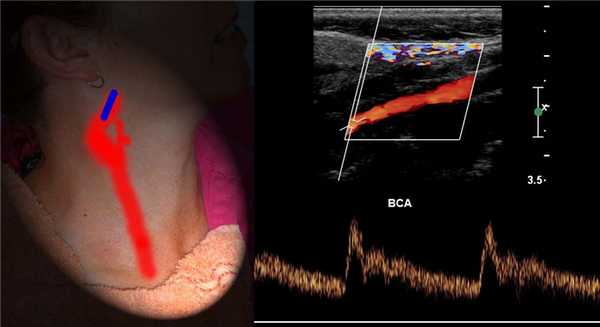

Из дуги аорты выходят ПГС, левая ОСА и ПКА. На уровне правого грудино-ключичного сочленения ПГС делится на правую ОСА и ПКА.

Оценивают дистальный отдел ПГС, ПКА, ОСА на всем протяжении, ВСА от устья до входа в череп, НСА в начальном сегменте, ПА в сегментах V1 и V2.

Для исследования ПГС датчик располагают в яременой вырезке, луч направляют вправо. ПГС делится на правую ПКА и ОСА. Устье левой ОСА и ПКА слишком глубоко, чтобы видеть.

ПА сканируют продольно кнутри от кивательной мышцы, от угла нижней челюсти до верхнего края ключицы.

Для исследования I сегмента ПА датчик смещают до ключицы. В норме ПА отходит от ПКА на уровне С7 и входит в костный канал на уровне С6.

Спектр ОСА имеет резкий подъем и узкий пик в систолу, низкий поток в диастолу, дикротический вырез в поздней систоле и ранней диастоле.

Спектр II сегмента ПА по форме похож на ВСА, Vps и Ved в 1,5 раза ниже, поток исключительно антеградный. Vps может снижаться на верхних отрезках, но не более 20%.